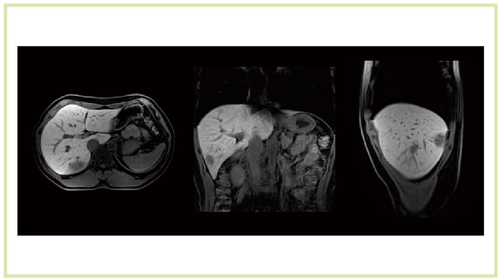

さらに,心臓MRIにおける3T装置の特徴として最も強調すべきは,SNRの高さをthin sliceに生かすことができることである。1.5T装置では,thin slice画像は実用的ではなかったが,3T MRIでは積極的に使えるようになった(図13,14)。thin slice 撮像のメリットを,われわれは心臓の遅延造影法として,whole heart late gadorinium enhancement法に用いることとした。マルチスライスCTの撮影のように,心臓を薄いスライス厚で撮像し,それを再構成することで,短軸像,長軸像,四腔断像など,いろいろな方向からの観察が可能になる。1.5T装置の場合,スライス厚が3mm,スライス間補間が1.5mmであったが,3T MRIではそれぞれ1.5mm,0.75mmとなり,高い空間分解能を持った再構成画像を得ることができる(図15)。

図14 肝細胞がん症例(Titan 3T) 肝細胞相 TR/TE=3.7/1.3 MX=588*640 NS=100 ST=2 Time=19s

図14 肝細胞がん症例(Titan 3T)

肝細胞相

TR/TE=3.7/1.3 MX=588*640 NS=100 ST=2 Time=19s